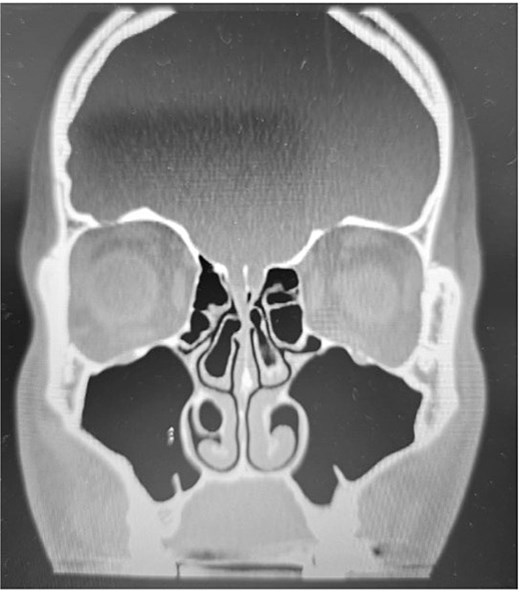

Clinical examination, including anterior rhinoscopy and nasal endoscopy, revealed a midline nasal septum and bilateral hypertrophy of the inferior and middle turbinates, with otherwise normal nasal mucosa. A CT scan of the paranasal sinuses in the coronal plane demonstrated bilateral pneumatization of the middle turbinates consistent with CB. Additionally, the right inferior turbinate was pneumatized, with communication to the ipsilateral maxillary sinus (Figs 1 and 2).

Paranasal sinus CT scan in the coronal plane demonstrating bilateral inferior concha bullosa with communication to the maxillary sinuses.